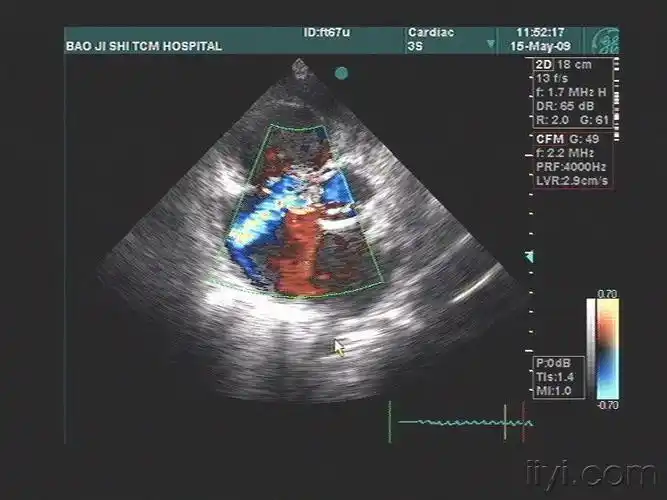

rvot 右室流出道 cs 冠状静脉窦)1, 左位上腔静脉;2, 左心房扩大超声

e,左冠瓣脱垂 超声示:右室流出道切面显示右冠状动脉窦呈袋状扩张

超声典型病例主动脉右冠窦瘤破入右室

房室瓣后方水平:与左心室二尖瓣环后方相平行的间隙为冠状静脉窦